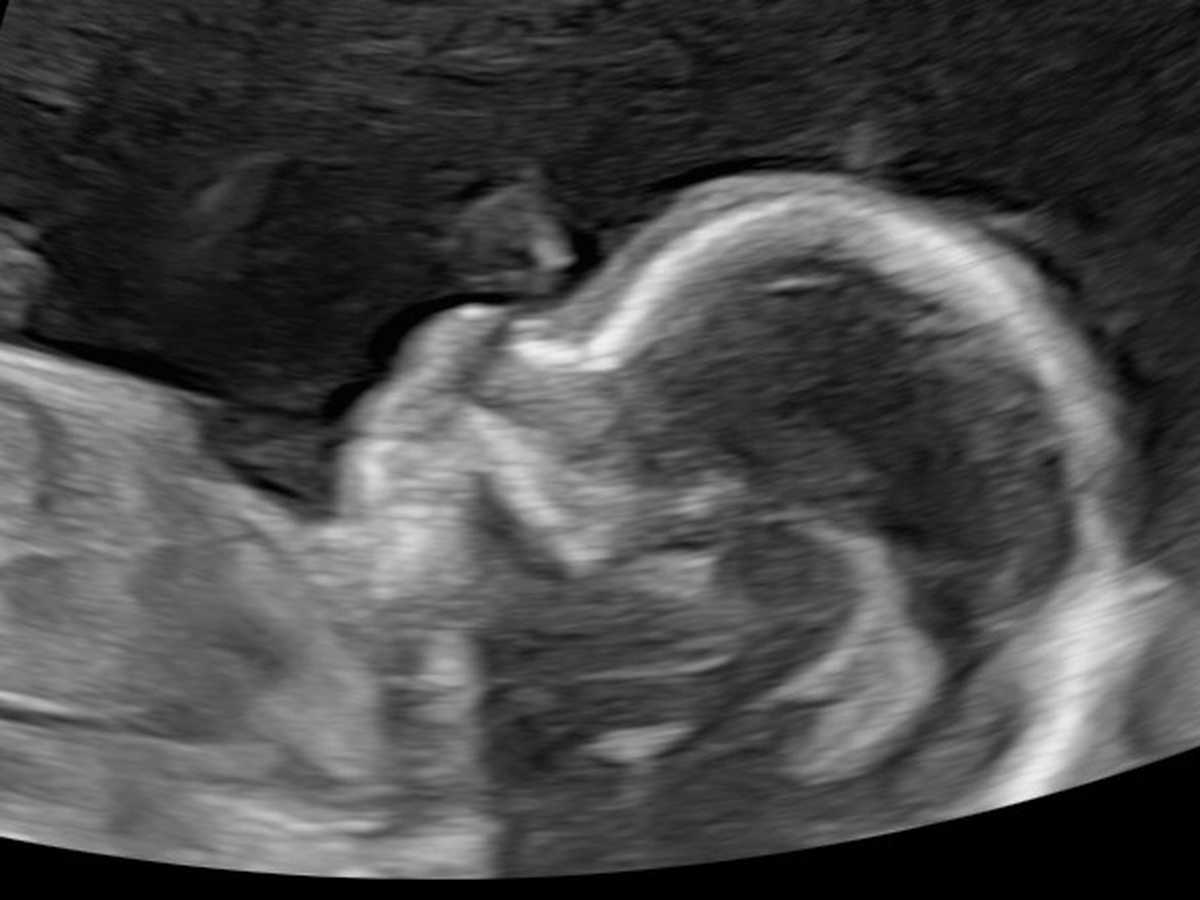

Sophie and Noah Banks are expecting another little girl…Marigold! During the anatomy scan they found out she has spina bifida myelomeningocele, the most severe form of spina bifida. This means as her spine was forming, her back did not close properly and her spinal nerves are outside of her body and being damaged by amniotic fluid, which they learned has also caused both of her feet to be clubbed. As of now her brain looks “normal” with little to no fluid seen in there…typically this isn’t the case. Right now (11/10/25) they are waiting to find out if they qualify for fetoscopic surgery to prevent more damage being done to her & repair her back. Surgery will require Sophie to stay months in Houston before birth & afterwards for NICU care. If she doesn’t get the surgery, Sophie will have to deliver either in Houston or Little Rock to have neurosurgeons & other specialized doctors near, which will also include a 4-6week stay before birth & NICU stay afterwards.